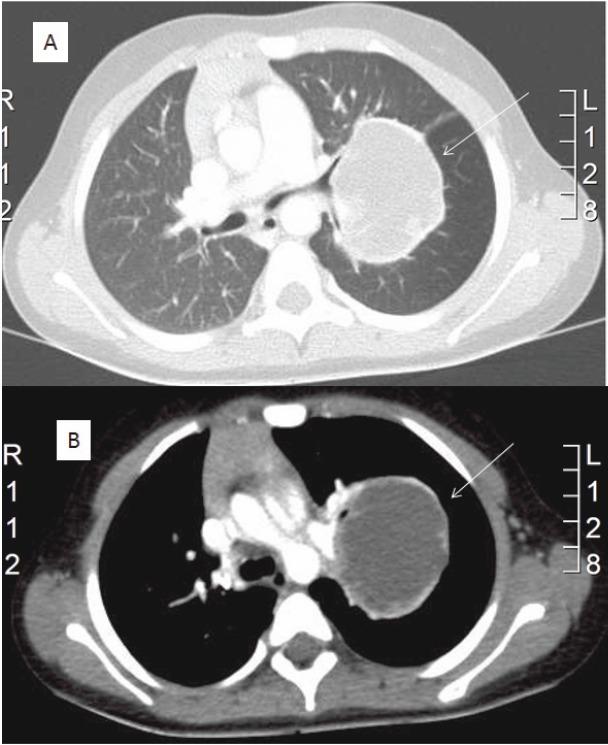

We report a case of primary extraosseous Ewing sarcoma (EES) of the lung in a four-year-old child. In the literature, there are only a few case reports of EES located in the thorax.

我们报告了一例4岁儿童原发性肺外尤文肉瘤(EES)的病例。在文献中,仅有少数关于位于胸部的EES的病例报告。